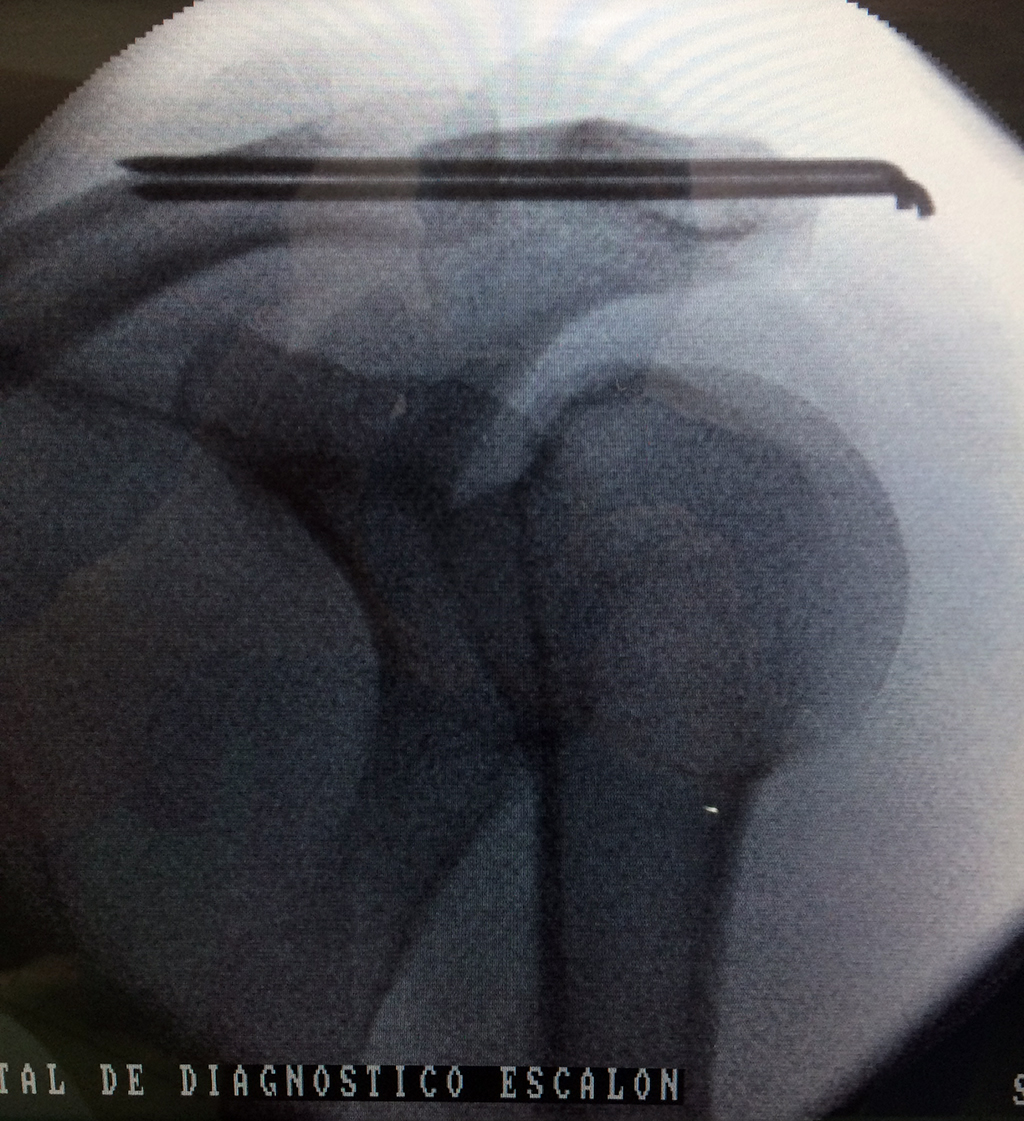

Cirugías de Hombros - Clavícula

La clavícula es un hueso largo, con forma de "S" itálica, situado en la parte anterosuperior del tórax. Junto con la escápula forman la cintura escapular. Se puede palpar por toda su longitud y se extiende del esternón al acromion de la escápula, siguiendo una dirección oblicua lateral y posterior.